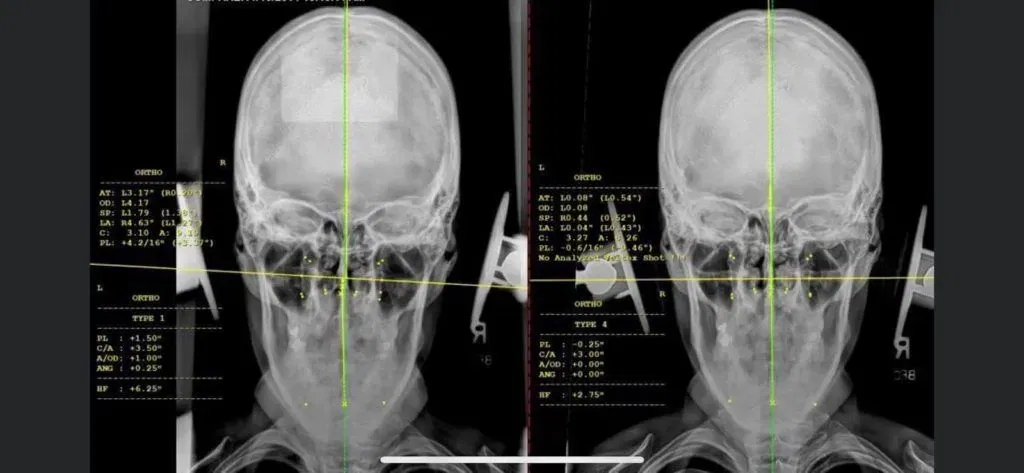

During the orthospinology treatment process, expect an initial consultation. On your first visit , upper cervical chiropractors may not administer an adjustment. Precise analysis and diagnostics are crucial to orthospinology, so chiropractors often take a few days to process results.

At your initial consultation, your upper cervical chiropractor may do a physical exam, digital x-ray analysis, maybe even a cognitive exam.

Before

After

Before-After

These before and after pictures from www.orthospinology.org show an average individual and how misaligned their spine may be before a spinal correction.